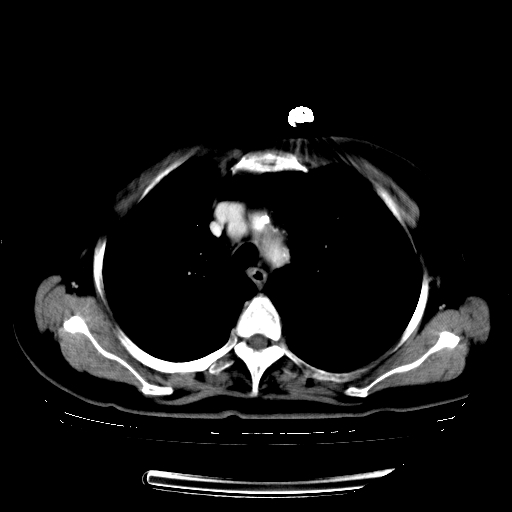

1.左上肺结核,部分纤维化。右肺中下叶部分肺不张,内见液化、坏死及点状钙化,右中下叶支气管壁增厚、管腔狭窄,见多个点状钙化,结合临床考虑支气管内膜结核,建议痰检查抗酸杆菌并参考血沉。两肺多个小圆点状高密度灶,境界模糊,多考虑结核肺内播散。但本人年龄较大首先应支气管镜检以除外右肺癌。

2.胸主动脉夹层。

一元论:内膜结核伴下肺阻塞性肺炎并双肺播散!另:主动脉夹层。右侧少量胸腔积液。